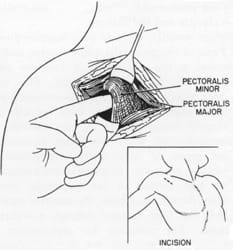

Wright also performed anatomic dissections to further understand the underlying mechanism of hyperabduction. He proposed that there were two different mechanisms, which might occur in isolation or in combination in different patients. First, Wright proposed that the space posterior to the pectoralis minor muscle would create “stretching, torsion, and pinching” of the vessels and brachial plexus only in hyperabduction. Second, he proposed that different arm motions, as demonstrated by Eden in 1939 and Falconer in 1943, would cause similar changes between the clavicle and the first rib.

Jere Lord and Peter Stone

Lord and Stone publish the first report on pectoralis minor tenotomy. They perform pectoralis minor tenotomy in addition to anterior scalenectomy in 5 patients, with good results in 4 patients

D. Silver recommends tenotomy of the pectoralis minor in selected cases of first rib resection. Vemuri et al suggest that a population of neurogenic TOS patients have predominant compression of the brachial plexus in the retropectoralis space. Thus, these authors suggest pectoralis minor tenotomy, either isolated or as an adjunct to first rib resection.

Pectoralis Minor Tenotomy

The pectoralis minor muscle arises from the anterior aspects of ribs 2 through 4, heads superiorly, and inserts on the coracoid process of the scapula. It acts to pull the scapula forward and down. This muscle also forms the anterior border of the retropectoralis space. Pectoralis minor tenotomy involves releasing it from its attachment on the scapula. Although tenotomy first introduced by Lord in 1956, the procedure did not become popular. Pectoralis minor tenotomy has been revived and popularized in the past 10 years. Some surgeons perform this procedure if a larger supraclavicular decompression and first rib resection fails. Other doctors consider this procedure as a primary treatment in some patients. Many doctors believe that the pectoralis minor muscle compresses the brachial plexus in some patients with neurogenic TOS. However, there are studies and there is anatomic data that contradicts this belief. Nonetheless, as the procedure gains popularity, further discussion is increasing our knowledge about this muscle.

Pectoralis minor syndrome

In 1956, Jere Lord and Peter Stone performed the first documented pectoralis minor tenotomy in 5 patients with hyperabduction syndrome. Although Lord and Stone apparently understood the importance of the retropectoralis space, the earliest mention of the name, “pectoralis minor syndrome” occurs in a paper published by Erich Lang in 1966.